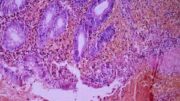

When we think about pathology, we often think it's all bout dead bodies and yucky stuff. But that's...

Hallux’s Pathology Puzzles: Josh’s Appendicitis

When we think of pathology, we might think of dead bodies - like in Professor Hallux’s favourite TV...